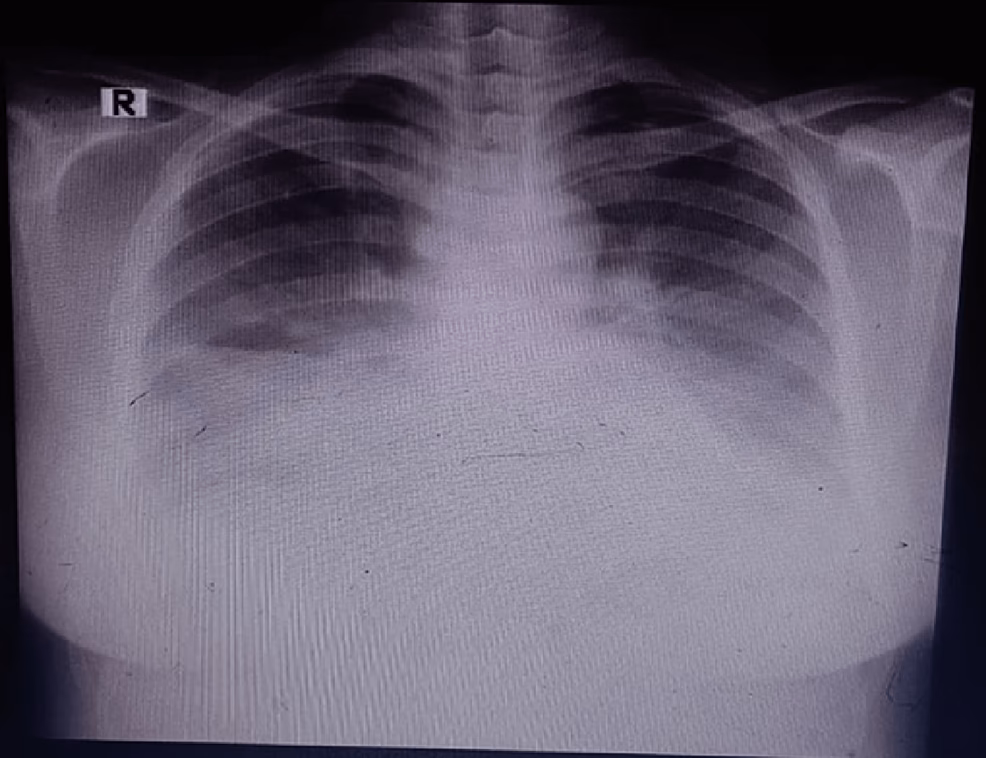

Hvis din læge har mistanke om lungebetændelse, vil diagnosen typisk blive stillet ved en fysisk undersøgelse, hvor lægen lytter på dine lunger. Det kan være nødvendigt med yderligere tests, såsom et røntgenbillede af brystkassen. Gravide kvinder vil blive beskyttet med et blyforklæde over maven for at minimere stråling til fosteret. En blodprøve kan også tages for at identificere infektionen.